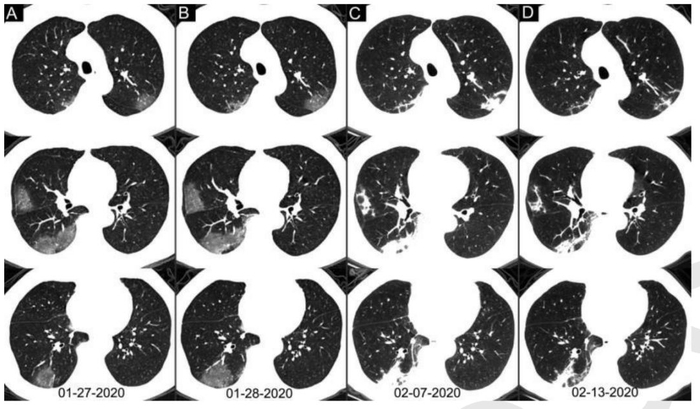

结合核酸检测和CT扫描分析,核酸检测从阴性到阳性的平均间隔时间为5.1±1.5天(范围4~8天),核酸检测从阳性转为阴性的平均间隔时间则是6.9±2.3天(范围4~15 天)。

60~93%的病例在初始核酸检测阳性之前(或同时)具有与新冠肺炎一致的初始CT阳性表现。42%(24/57)的病例在核酸检测结果转为阴性之前,其胸部CT扫描已经显示病灶吸收。

早期出现小斑片或间质性改变,常有磨玻璃阴影;

病灶主要位于胸膜下。随着病情进展,病灶常为双肺多发。

随着病情进展,CT失去特异性,不容易鉴别与一般的肺炎。

特别是后期变成“白肺”,没有之前的影像学做对比,更是没办法做出准确的诊断。